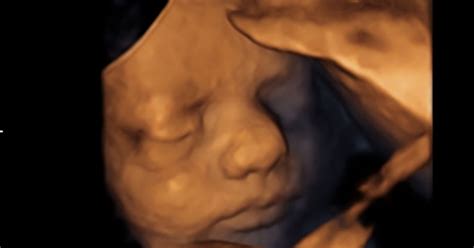

- Ultrazvok: Ta test lahko potrdi spontani splav s preverjanjem srčnega utripa ploda ali prisotnosti rumenjakove vrečke.